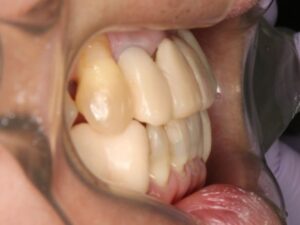

矯正治療前の歯並びでは、被せ物だけでバランスの取れた歯並びの歯に治そうと思っても難しいですが、矯正後の歯並びでは見た目もキレイで、食べ物も噛み易い歯に治せます。

治療前は反対咬合で前歯がかみ合っていませんでしたが、ワイヤーでの矯正治療だけで下顎は正常咬合の骨格まで後へ下がりました。反対咬合の人の場合、外科矯正になる事も多いのですが、当院で行っているMEAWのワイヤー矯正で手術が必要な外科矯正を避ける事が出来てよかったです。

この後は、最終的な被せ物と義歯の作製へ治療は進みます。